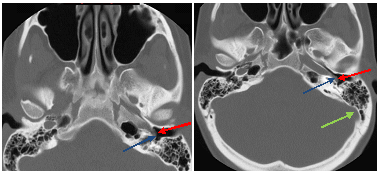

Figure 1: Axial images from a temporal bone CT demonstrate a tubular soft tissue mass (red arrow) inseparable from the petrous portion of the internal carotid, overlying the cochlear promontory (blue arrow) and directed posterior to anterior. The sigmoid sinus (green arrow) is unremarkable.

Imaging demonstrates absence of the vertical portion of the carotid canal, an intact petrous carotid and an atypical course of the ICA and a middle ear soft tissue mass. The diagnosis can be confirmed with a CT or MR angiogram which demonstrates the vascular nature of this mass.